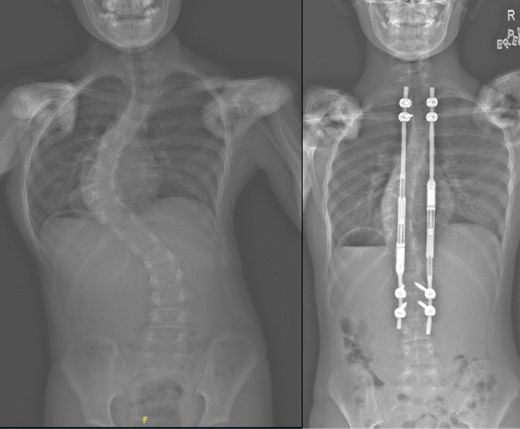

The Centre also acquired the first EOS scanner in Singapore. This unique radio-imaging system, based on Nobel prize-winning technology, allowed for whole body scanning using low dose X-rays and has become essential in the assessment of spinal deformities in adults and children.

Amongst other achievements, the Spine group introduced interval halo-gravity traction for the treatment of very severe scoliosis curves, the use of O-arm navigated surgery employing paediatric radiation doses, the use of 3D printing in planning for complex spine curvature correction, the use of microdose EOS X-rays for scoliosis assessment, the intra operative use of spinal cord ultrasound post decompression to assess the adequacy of neural decompression and the introduction of endoscopic spine surgery.